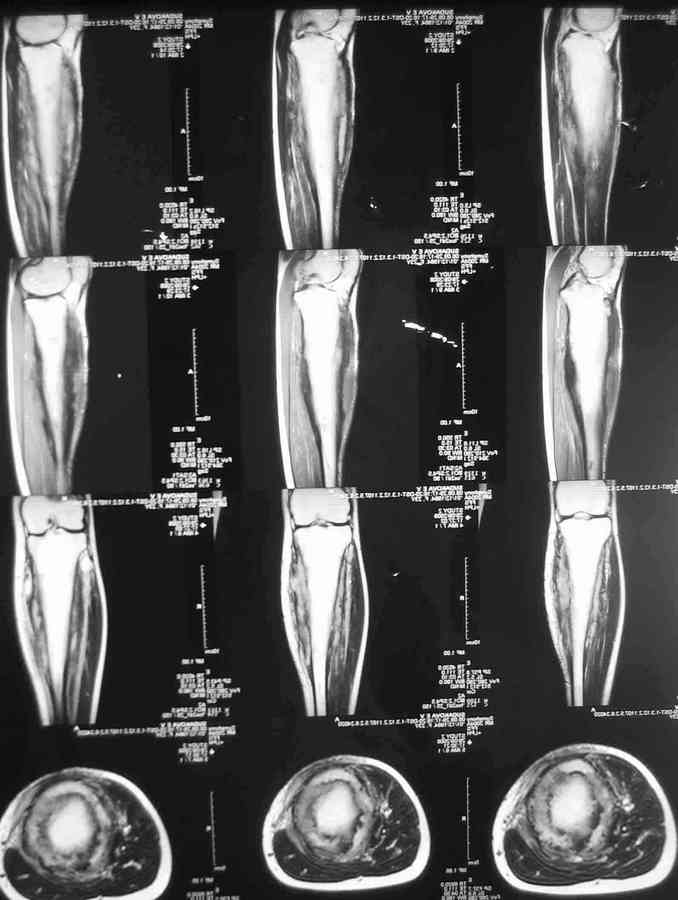

Господа, обратилась девушка 20 с небольшим лет.Больна с 2002 года. остеомиелит Гарре. Подтвержден гистологически.